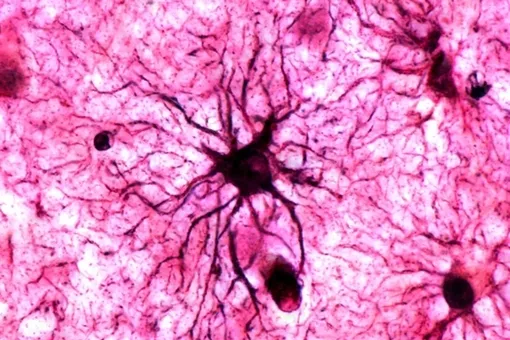

Астроциты — это звездообразные клетки, которые составляют примерно половину всех клеток центральной нервной системы. Долгое время считалось, что они выполняют лишь вспомогательные функции: доставляют питательные вещества к нейронам, удаляют отходы и поддерживают структуру мозга. Однако последние исследования показали, что астроциты способны воспринимать нейротрансмиттеры и модулировать активность нейронов.

Основное отличие астроцитов от нейронов — скорость реакции. Нейроны обмениваются сигналами за миллисекунды с помощью электрических импульсов. Астроциты работают гораздо медленнее, их молекулярные изменения разворачиваются в течение часов и дней. Это не недостаток, а особенность: астроциты связывают события, разделенные во времени, создавая своего рода молекулярную память о прошлом опыте, которая влияет на то, как мозг обработает будущие события.